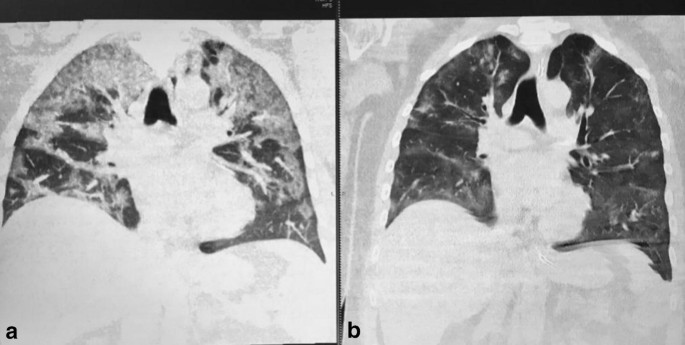

At admission, the patient had fever, dry cough and dyspnea. He was tachypneic (34 bpm) with an oxygen saturation of 88%. Quickly, the patient developed an acute respiratory distress syndrome and was urgently intubated on the same day of admission. The chest CT (computed tomography) scan showed a bilateral interstitial pneumonia (Fig. 1a) and he was positive for Sars-Cov-2 (nasopharyngeal swab). Laboratory testing showed increased levels of CRP (C-reactive protein) 2386 mg/l (normal value; 0.0–5.0 mg/l), LDH (lactate dehydrogenase) 890 U/l (normal value; 240–480 U/l), ferritin 6045.6 ng/ml (normal value; 30–400 ng/ml) and D-dimer 2890 ng/ml (> 500 ng/ml). Hydroxychloroquine,lopinavir/ritonavir,ceftriaxone and low-molecular-weight heparin were administred. Five days later, the patient’s clinical conditions deteriorated and we decided to administer an intravenous dose of tocilizumab (8 mg/kg). A second infusion at the same dosage was repeated after 12 h. His ventilation conditions improved day by day. One day after infusion of tocilizumab, CPR, LDH, ferritin and D-dimer levels went down (87.9; 631; 3915.5; 778 respectively).

a Chest CT scan showing ground-glass opacities in the upper lobes of the lungs. b Chest CT scan showed a significant absorption of lung lesions after tocilizumab treatment

After 3 days, we repeated CT chest scan that showed an impressive improvement (Fig. 1b). Two days later, the patient was extubated and was transferred to pulmonary medicine unit with a normal value of LDH, a CPR of 11.9 mg/l, a ferritin value of 1505.9 ng/ml and a D-dimer of 1630 ng/ml. Interleukin-6 levels were measured 1 day before infusion of tocilizumab and after 3, 5 and 7 days showing a progressive decrease from 201 pg/ml to 139, 42 and 33 pg/ml, respectively (1–13.1 pg/ml are considered normal values in Caucasians). Twenty days after admission, the patient was discharged without any need for oxygen supplementation.